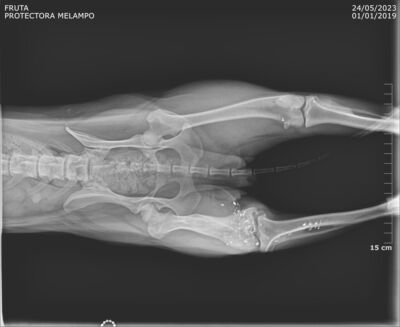

Update 26.05.2023

Fruta wurde kastriert und ihr alte Verletzung wurde dabei auch gleich geröngt. Dabei kam heraus, dass Fruta eine Schussverletzung hat und immer noch Schrot im Bein hat. Die Röntgenbilder sind weiter unten zu finden.

Fruta’s Hinterbein wurde beim Spezialisten abgeklärt. Das Bein ist steif, sie hat aber keine Schmerzen. Es stört sie auch nicht, sie läuft, rennt und hüpft auch ohne Probleme aufs Sofa.